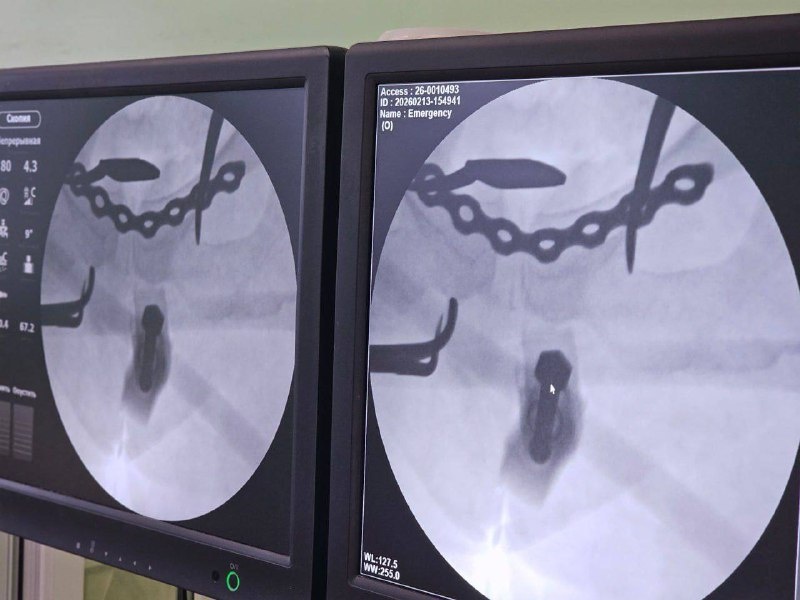

В Воронеже врачи успешно прооперировали женщину, получившую тяжелую травму таза после падения с тюбинга на высокой скорости. Пациентка, 41-летний житель города, была доставлена в больницу скорой медицинской помощи №1 с множественными переломами крестца и разрывом лонного сочленения.

Спустя несколько часов после госпитализации хирурги провели срочную операцию длительностью всего 20 минут. В ходе вмешательства использовали аппарат внешней фиксации для восстановления правильной позиции костных фрагментов. Благодаря своевременно оказанной высококвалифицированной помощи состояние больной стабилизировалось уже через несколько дней.

Далее специалисты применили винты и титановую пластину для надежной фиксации поврежденной области. Через некоторое время пациентка полностью восстановилась и вернулась к обычной жизни.